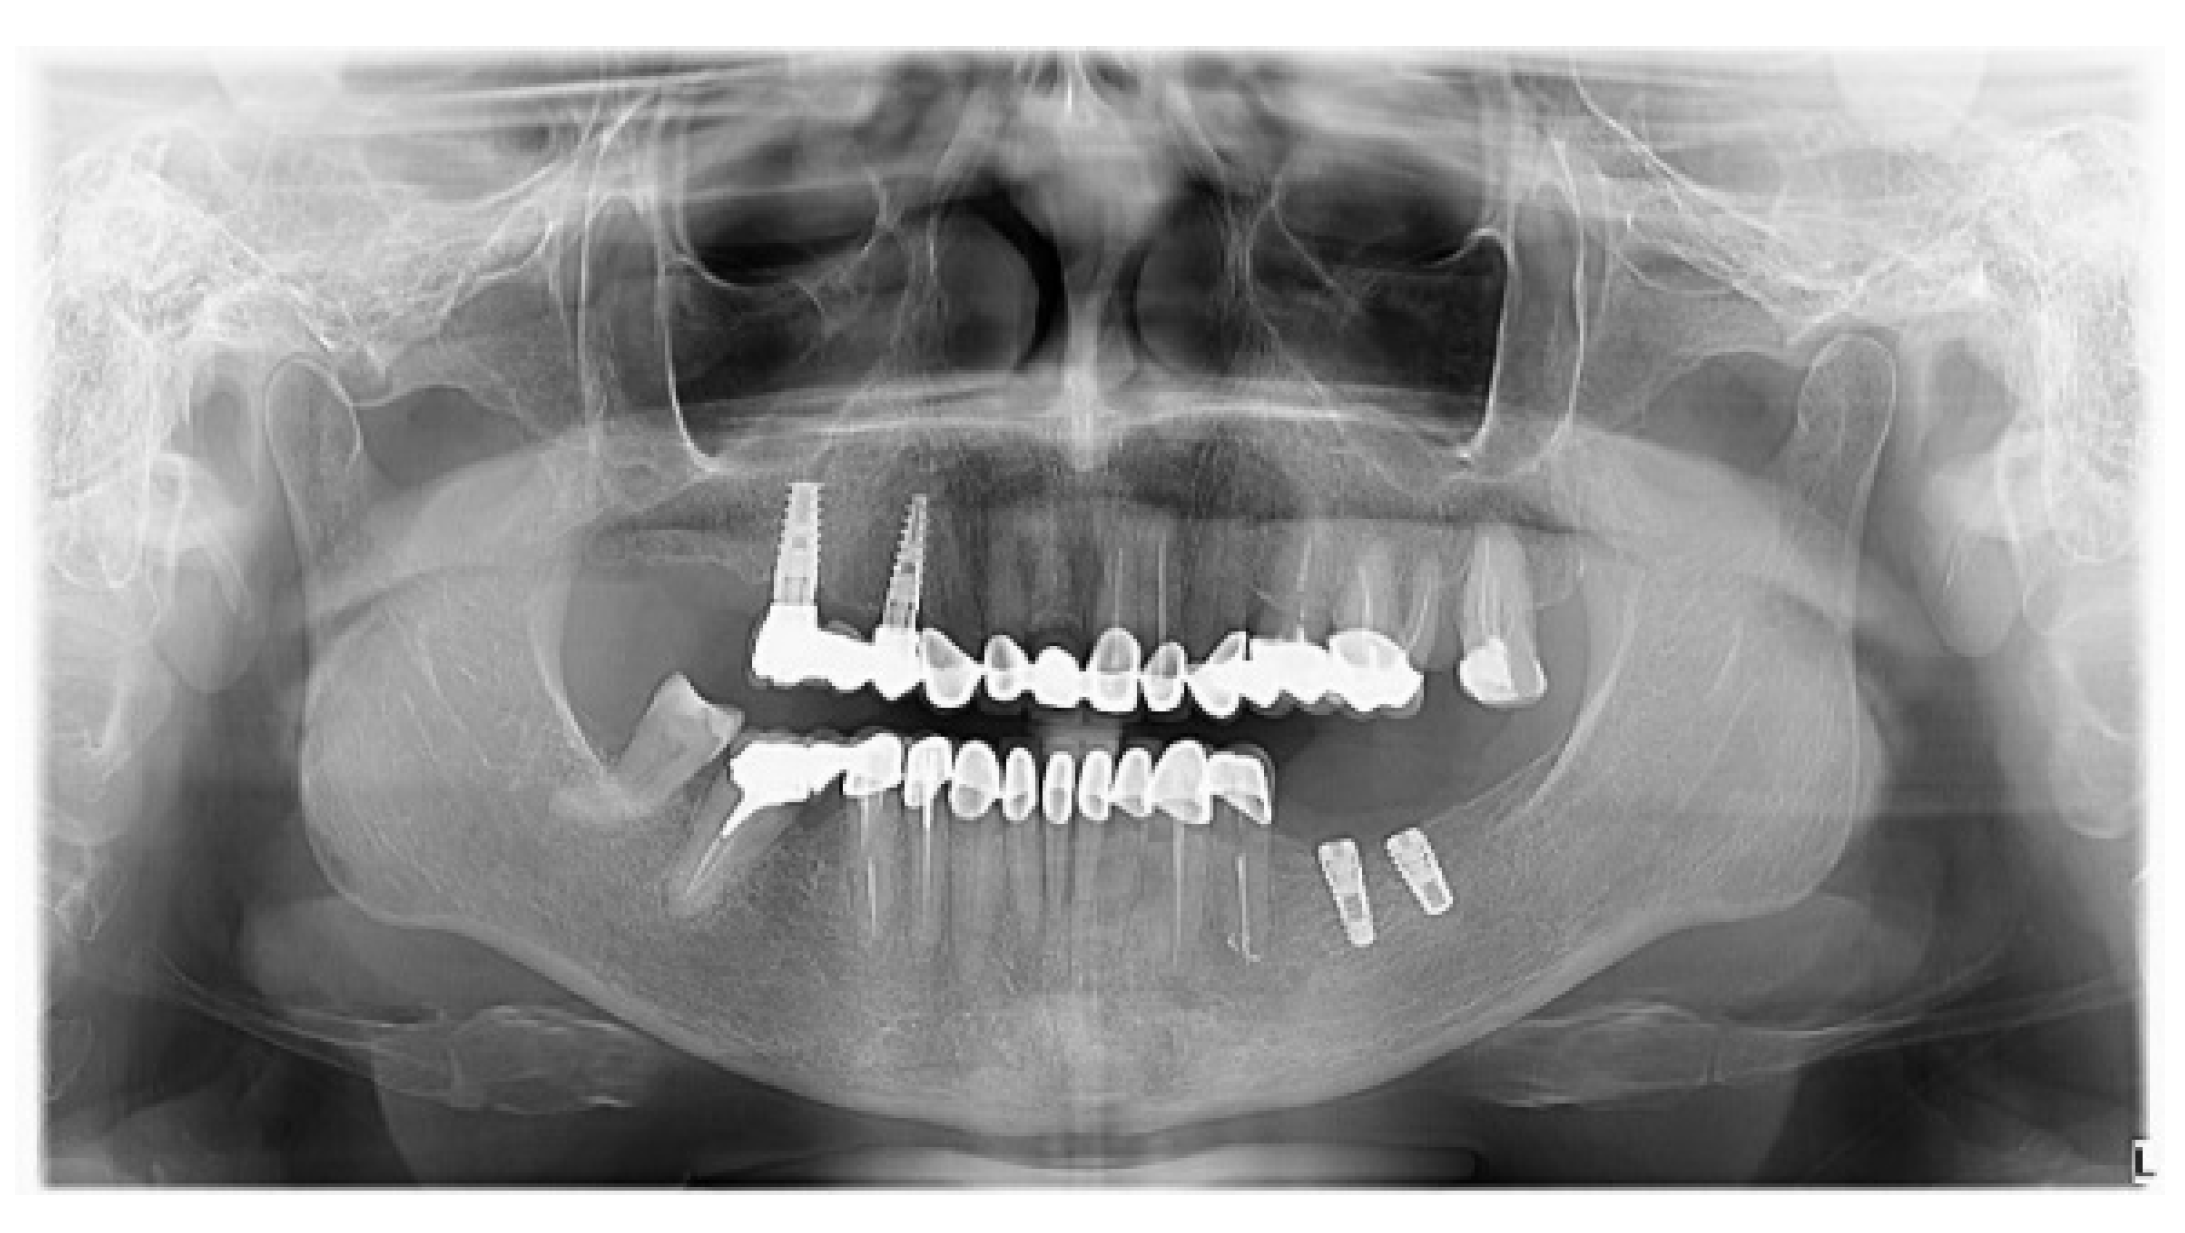

2. Case Report